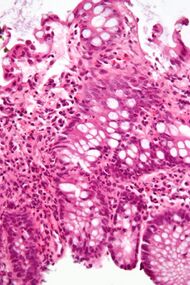

Micrograph showing

cryptitis in a case of Crohn's disease. H&E stain.